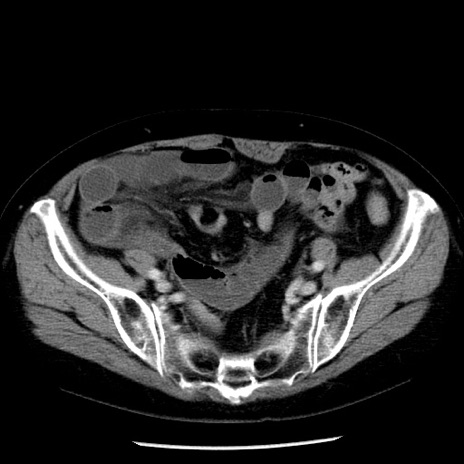

症例13(横断像)

【症例】70歳代女性

【主訴】腹痛、嘔吐

【現病歴】15時間程前(昨晩)より腹痛あり。今朝になっても症状の改善なく、嘔吐あり。腹痛も増悪あり、救急外来受診。

【既往歴】子宮癌全摘術後

【身体所見】意識清明、BP 121/72mmHg、P 74bpm、SpO2 100%(RA)、腹部:平坦・軟、腸雑音ほぼ聴取せず。下腹部・心窩部・臍左上に圧痛あり。反跳痛なし。

【データ】WBC 10600、CRP 0.15